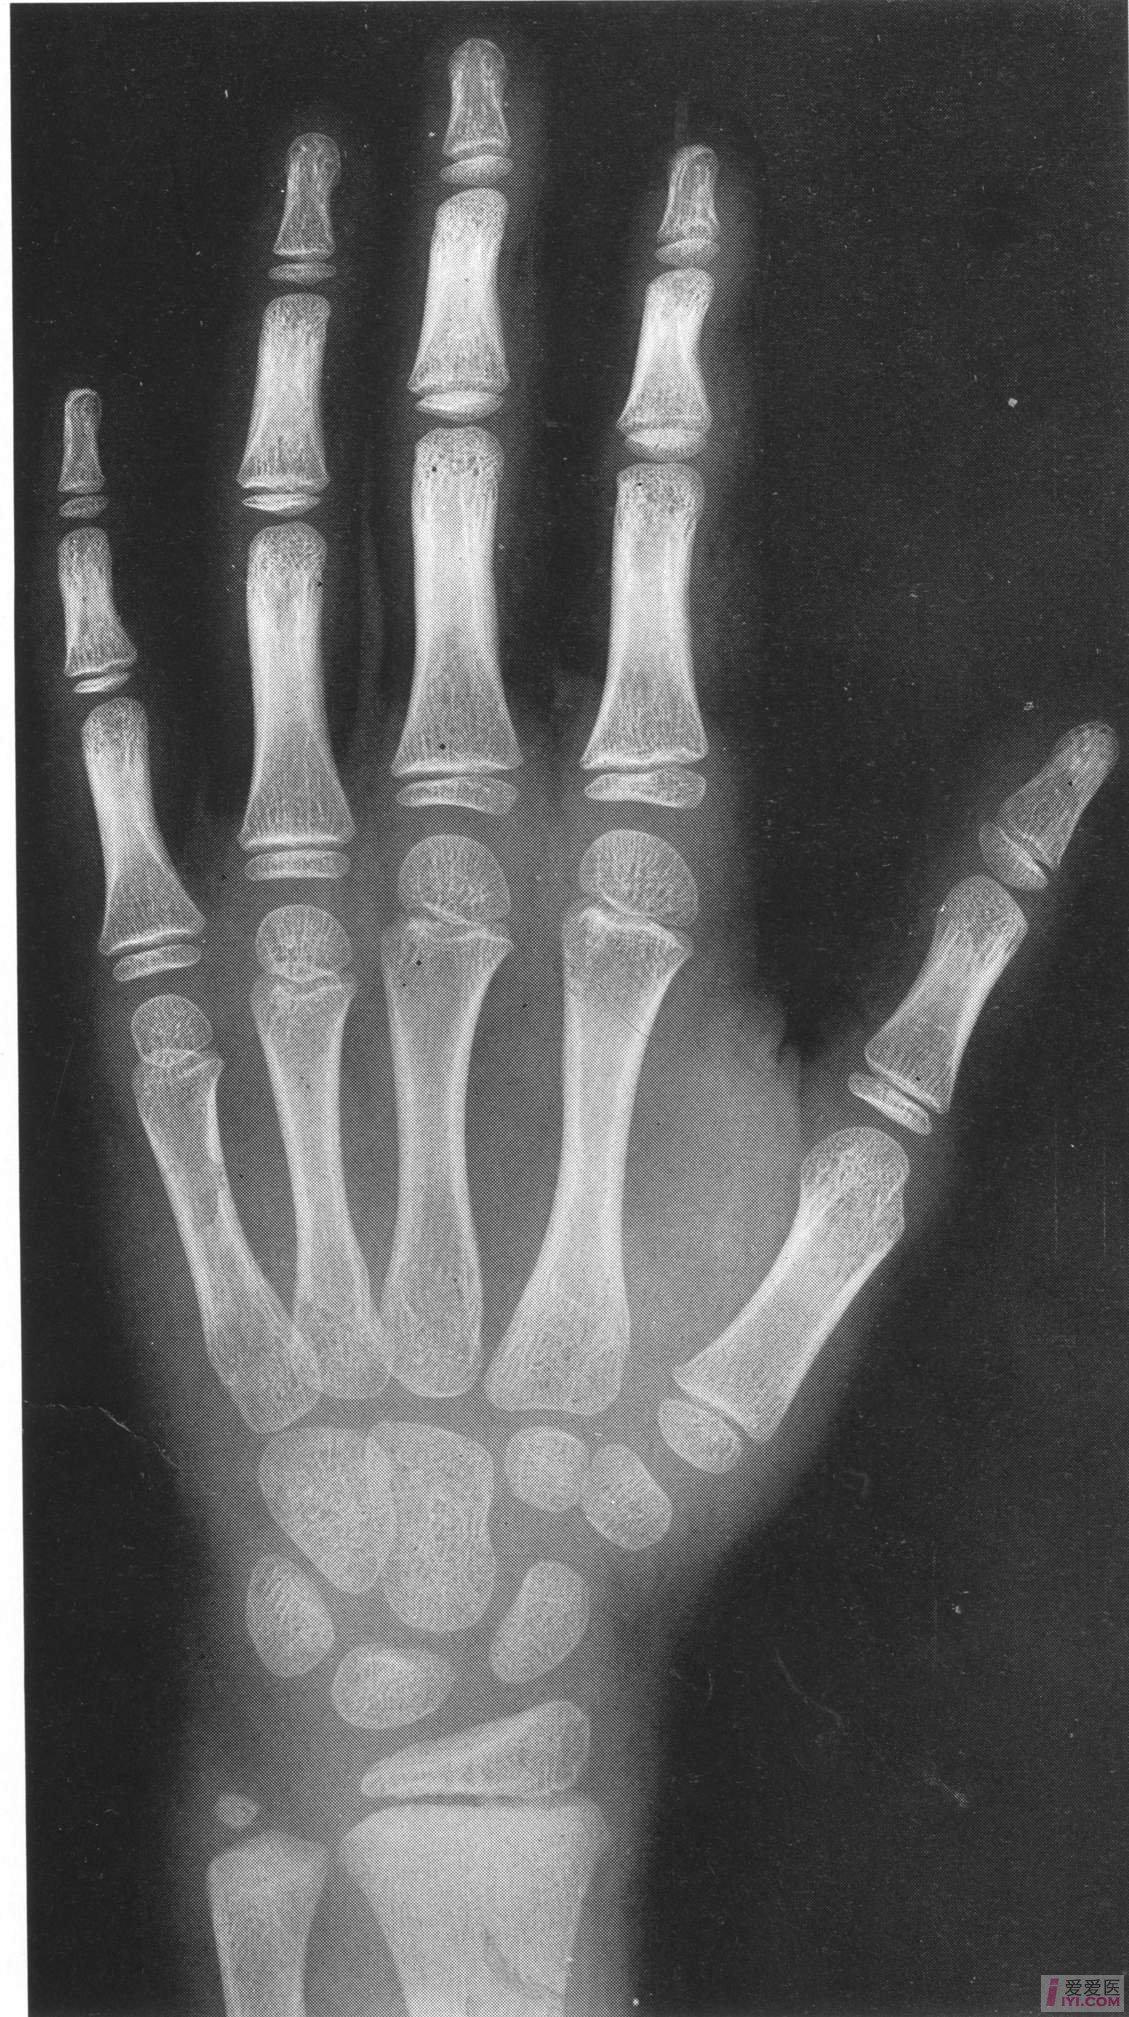

女性标准骨龄图谱 6岁.jpg